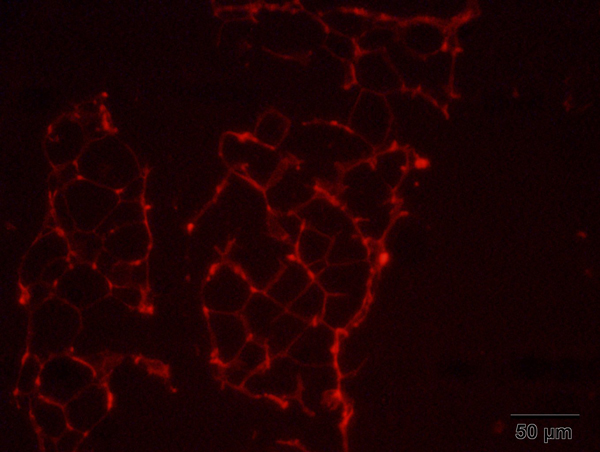

ایمونوهیستوشیمی و ایمنوفلورسنت (IHC) برای تعیین آنتی ژنی خاص در بافت بکار میرود.

اساس ایمونوهیستوشیمی، ردیابی آنتی ژن ها در برش های بافتی با استفاده از آنتی بادی های کنژوگه شده با مواد فلئوروسنت، آنزیم ها و عناصر رادیواکتیو می باشد که پس از اتصال آنتی بادی کنژوگه شده به آنتی ژن هدف در سطح بافت و تولید یک محصول رنگی طی واکنش هیستوشیمی با میکروسکوپ نوری یا میکروسکوپ فلوروکروم و با نور ماوراء بنفش (UV) می توان محصول رنگی را که در واقع محل بیان آنتی ژن موردنظر است، تشخیص داد.

برای تصویر برداری از میکروسکوپهای Inverted Microscope - IM-3 Optika ITALY- و Fluorescence Microscope - BM-600 LED - Axiom – Germany و Olympus BX50 استفاده میشود

Propidum Iodide Staining of Hippocampus